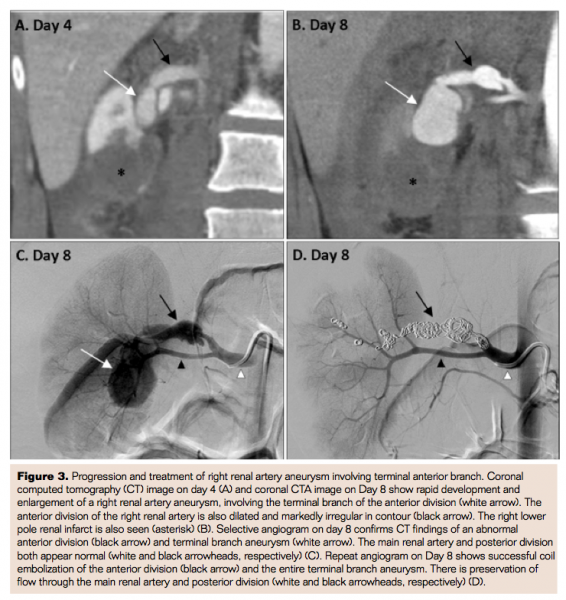

On day 8 of hospitalization, CT angiography (CTA) was performed for imaging follow-up and demonstrated increasing right perinephric hematoma and grossly similar appearance of the bilateral renal artery abnormalities (Figure 1C). There was, however, a new large saccular aneurysm involving the terminal branch of the anterior division of the right renal artery, which had developed since day 4 (Figures 3A and 3B). There was subtle contour irregularity of the aneurysm, suggestive of aneurysm rupture. In addition, CTA showed new fusiform aneurysms of the left and right hepatic artery branches (Fig 2 C). Because of the newly developed saccular aneurysm and the increased perinephric hematoma, Interventional Radiology (IR) was consulted for emergent coil embolization of the aneurysm.

Selective angiogram of the right renal artery revealed marked contour irregularity of the anterior division and a large saccular aneurysm in the terminal branch, both corresponding to the CTA findings (Figure 3C). Next, multiple metallic conventional and detachable microcoils were deployed through the main segment of the anterior division. Repeat angiogram confirmed successful and uncomplicated coil embolization of the main anterior division and the aneurysmal segment, with preservation of flow in the main renal artery and entire posterior division (Figure 3D). Following the procedure, the patient was transferred back to the ICU and remained hemodynamically stable.